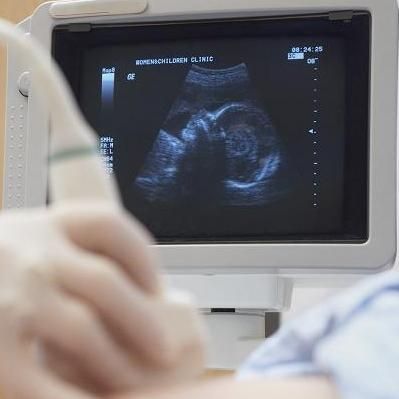

女性怀孕后,都会定期做B超检查。做B超既能监测胎儿生长发育,又能筛查胎儿有无畸形。不过,很多准妈妈表示看不懂B超单。

如何看懂超声报告?徐州市妇幼保健院超声科副主任左云鹏,带领准妈妈们解读超声报告上的关键字。

当你第一次通过B超看到胎宝宝在肚子里的景象,一定非常高兴,她(他)在踢腿、吃小手、做鬼脸儿,此时除了关注宝宝的这些小动作之外,你一定还会关心宝宝在子宫里生活得好不好。

但是,当拿到B超单的时候,准妈妈们想通过那些数据了解孩子的讯息恐怕很难,因为太专业了,犹如读天书,不知所云。

据左云鹏主任介绍,随孕周不同,医院产科超声报告单报告的内容也会不一样。早孕期超声报告单一般包括胚囊、胚芽及心搏,中晚孕期一般包括胎位、胎心率、双顶径、股骨长、胎盘、羊水、脐动脉S/D比值等检测数据。这些方面的测量数据是比较多的,而且不同的孕周有不同的正常值标准。